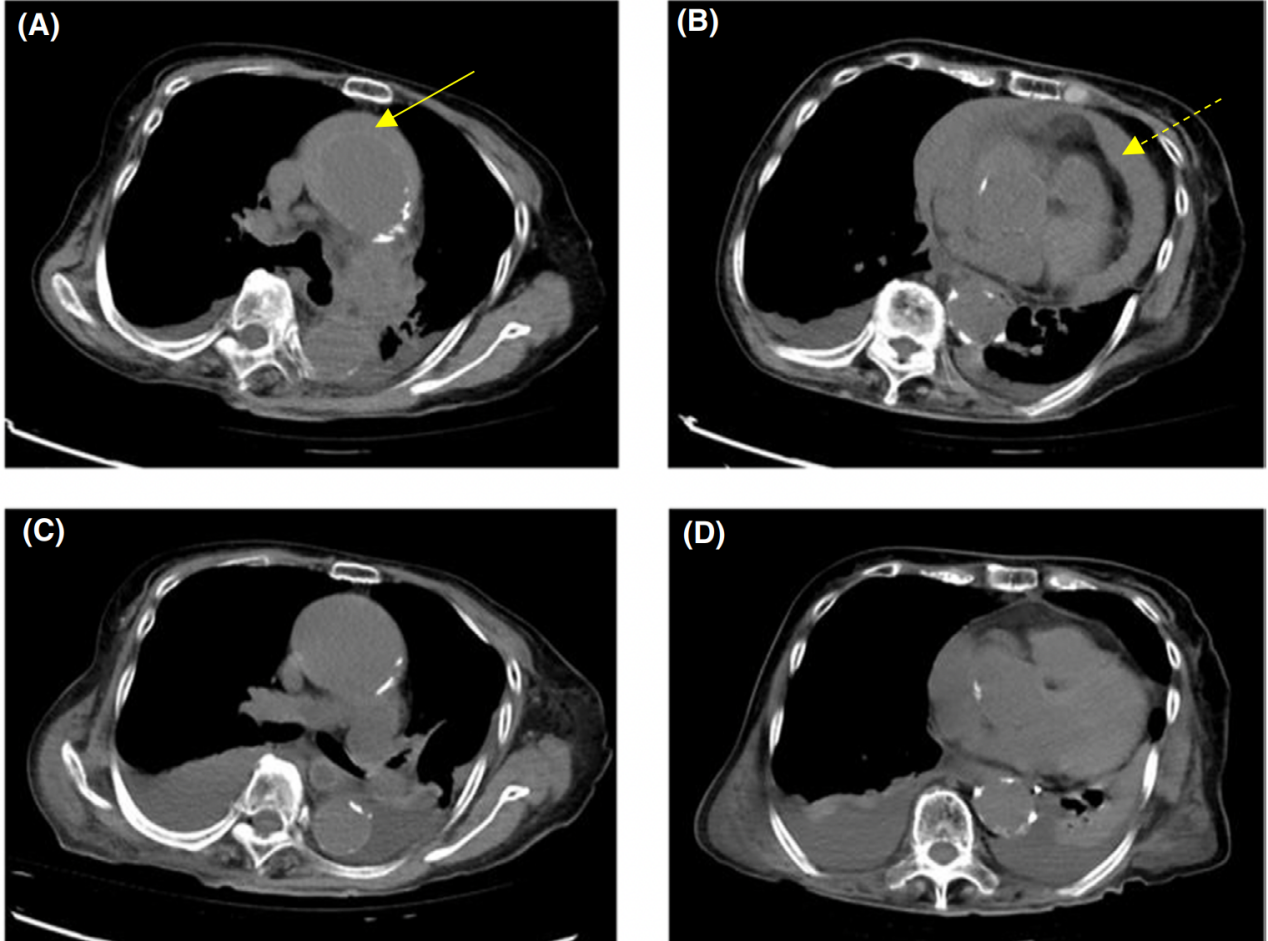

考虑到患者的肾功能,决定不使用造影剂。在无心电图门控的情况下进行了无造影计算机断层扫描(CT)来评估主动脉的结构。CT示主动脉壁有一个充满血肿的假腔(图2A-B);患者被诊断为急性主动脉夹层(AAD)合并心脏填塞。由于血流动力学不稳定,考虑手术治疗。然而,由于患者的高龄、痴呆、慢性肾脏疾病等因素,围手术期风险被认为是非常高的。

图2: 非收缩胸部计算机断层扫描(CT)。A, B,入院时胸部CT显示一个充满血肿的假腔,呈新月形,主动脉壁后呈高衰减区(新月形高衰减血肿),降主动脉水平有心包积液。C, D,入院后第8天胸部CT示升主动脉周围血肿吸收,心包积液减少。←,表示高衰减血肿;⇠,显示心包积液

住院第3天开始停用预防康复,第8天进行CT扫描确认病情。经证实,心包积液减少,升主动脉夹层缩小(图2C-D)。第13天再次进行CT评估,患者康复进展良好。随后从重症监护室出院。术后病情持续稳定,第62天转院持续康复。